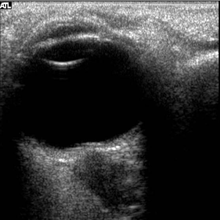

The astronauts afflicted with long term visual changes and prolonged intracranial hypertension have all been male, and SOS may explain this because in men, the sternocleidomastoid muscle is typically thicker than in women and may contribute to more compression. The reason that SOS does not occur in all individuals may be related to anatomic variations in the internal jugular vein. Ultrasound study has shown that in some individuals, the internal jugular vein is located in a more lateral position to Zone I compression, and therefore not as much compression will occur, allowing continued blood flow.